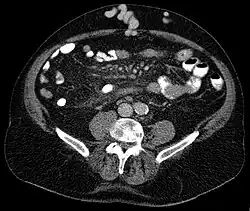

Axial CT showing portosystemic collateral circulation via the umbilical vein: caput medusae in liver cirrhosis